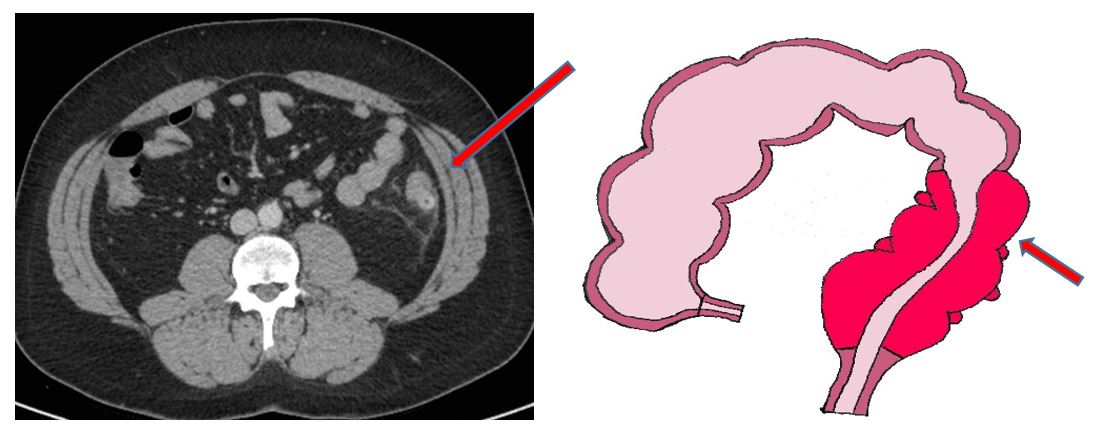

Elle se manifeste par une douleur dans le bas ventre, plutôt à gauche, avec de la fièvre, une constipation réflexe ou au contraire une diarrhée, et peut être favorisée par la prise d’AINS ou anti-inflammatoires. Un bilan sanguin vous sera prescrit et montrera des signes d’infection avec leucocytes augmentés et CRP élevée. Un scanner est fait en période aigüe et confirme l’inflammation du colon, avec une paroi épaissie et la présence de complication (abcès, bulles d’air extradigestives, péritonite).

En cas d’abcès, un drainage par voie cutanée par un radiologue (sous anesthésie locale sous contrôle échographique ou scannographique) peut être réalisé en fonction de sa taille et de sa localisation.